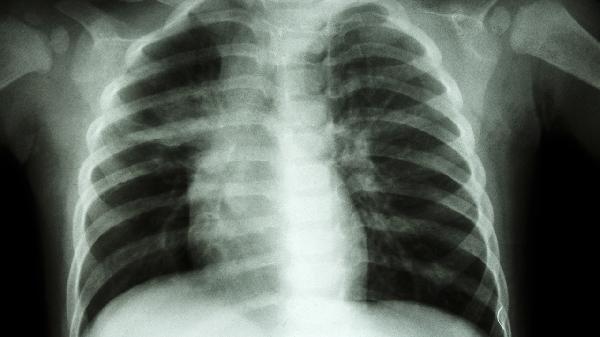

肋骨外翻屬于胸廓畸形的一種。肋骨外翻是指肋骨下緣向外突出,通常由肋軟骨發(fā)育異常、長(zhǎng)期姿勢(shì)不良等因素引起,可能伴隨胸廓形態(tài)改變或呼吸功能受限。

先天性肋骨發(fā)育異常如馬方綜合征、軟骨發(fā)育不全等疾病也可導(dǎo)致肋骨外翻,這類患者多合并其他骨骼系統(tǒng)畸形,需通過(guò)影像學(xué)評(píng)估胸廓三維結(jié)構(gòu)。極少數(shù)創(chuàng)傷后肋骨畸形愈合或胸壁腫瘤壓迫也可能引發(fā)局部肋骨外翻,需結(jié)合病史鑒別診斷。